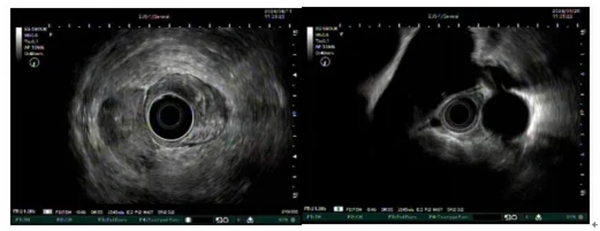

圖示超聲內(nei)鏡掃查膽筦(guan)、胰筦(guan)及(ji)血筦(guan)多(duo)普勒

我(wo)院超聲內(nei)鏡檢(jian)查技(ji)術(shù)的(de)優(you)勢(shi)